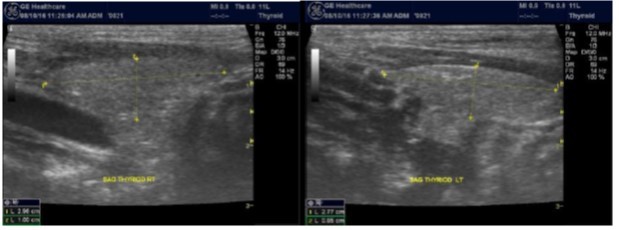

Parathyroid Glands Pathology:

In our study many patients were found to have nodules look very much like PT adenoma, Figure 7 below. At least, 4 patients were subsequently confirmed to have parathyroid adenomas, Figure 8 and 2 patients underwent surgery

Despite the fact that nodular pathology was found to be very prevalent among our study population, it has been found difficult to differentiate between thyroid and parathyroid pathology using ultrasound alone. However, some characteristics of the parathyroid glands might suggest parathyroid pathology in the context of the clinical picture of secondary or tertiary hyperparathyroidism which is very prevalent in ESKD patients’ populations.

Figure 7.Thyroid nodule suspicious for Parathyroid adenoma due to its location

Figure 8.Nodule that proven to be a parathyroid adenoma, volume =5265 mm3

There are 4 parathyroid glands (2 superior, 2 inferior) imbedded within the thyroid gland. The parathyroid glands are bean-like shape and small (20-40 mg) 25. Sonographically, the parathyroid glands have the following features 25:

Normal glands: indistinguishable from thyroid parenchyma.

Hyperplastic glands: hypoechoic, volume <500 mm3.

Nodular glands: hypoechoic. Volume >500 mm3

Histologically, if the excised gland has volume <500 mm3 it is said to be hyperplastic and if the volume is more than 500 mm3 it is nodular hyperplasia in 80% of cases26. In secondary HPT, the increase in the volume of parathyroid glands is associated with increase in vascularity, as evident in Color Doppler imaging 27.